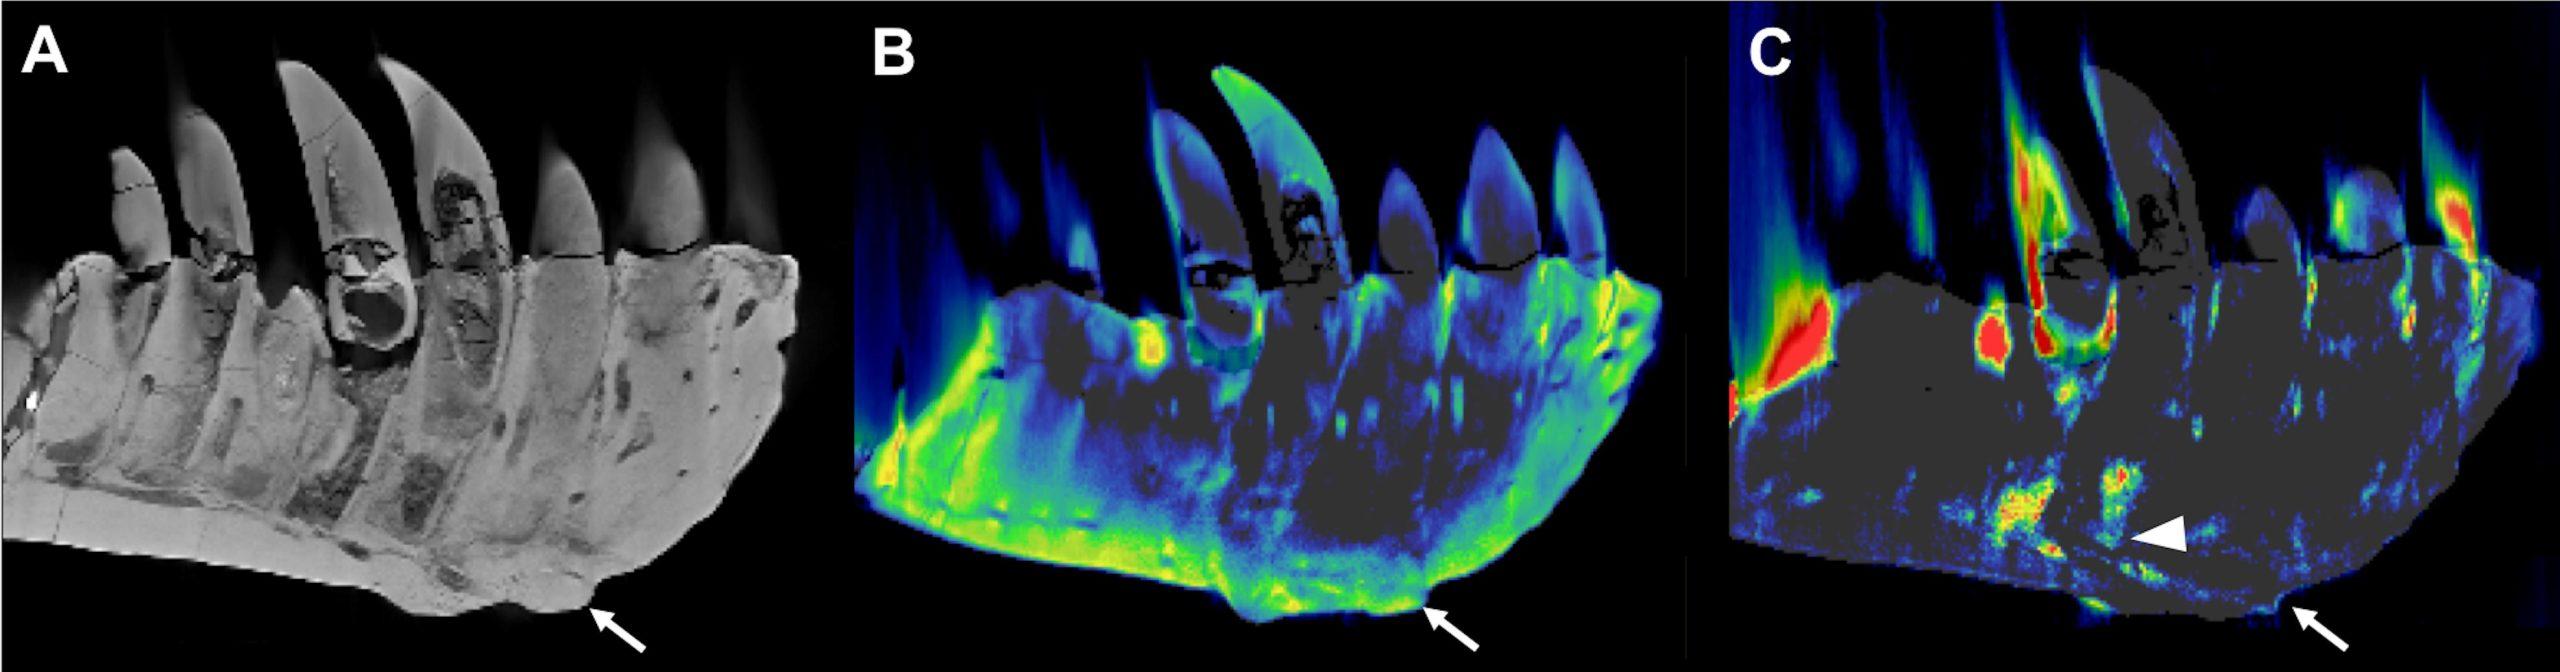

左侧牙床的含牙部分的CT重建。(A)常规CT图像的重建,在侧视图中显示了保存良好的解剖结构,如替换的牙齿。箭头所指的是第3-5个牙根水平的腹侧表面的病灶外植体--从组织表面伸出的异常生长。(B)基于DECT的钙物质图显示了均匀的矿物质分布,而(C)氟物质图显示在外植体中心和相邻牙根(箭头)有明显的矿物质堆积。

在目视检查和CT成像时,左牙显示增厚,其表面有一个肿块,延伸到一颗牙齿的根部。DECT检测到该肿块中氟元素的大量积累,这一发现与骨密度下降的区域有关。肿块和氟元素的积累支持了肿瘤性骨髓炎的诊断,这是一种骨感染。